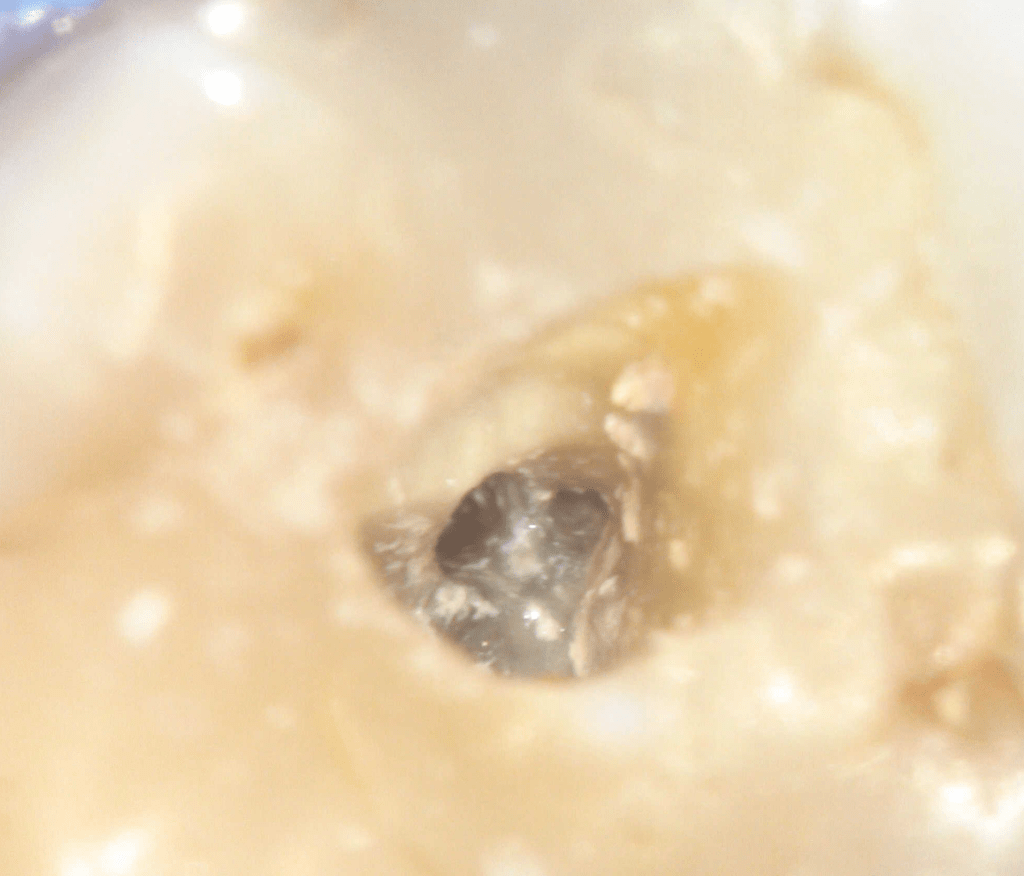

Fisura, remoción amalgama para explorar